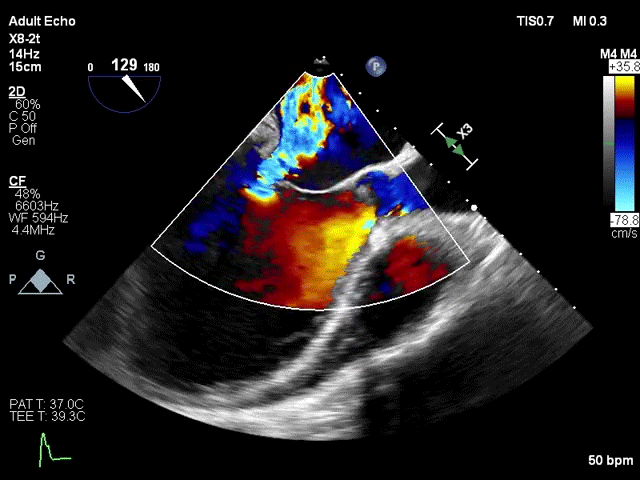

术前超声评估

该例患者为57岁男性,因扩张型心肌病合并严重心功能不全,并伴有高尿酸血症、高脂血症等疾病。超声心动图评估提示二尖瓣重度反流、轻微主动脉瓣反流与轻微三尖瓣反流,LVEDD 83mm,LVESD 73mm,LVEF 34%。二尖瓣反流机制为功能性反流,有效反流口面积为0.49cm²,反流量93mL,瓣口面积为6.7cm²。